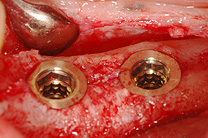

Ein Implantat ist eine schraubenförmige, künstliche Zahnwurzel aus Titan. Das Implantat dient als Fundament für einen Zahnersatz, entweder eine festsitzende Krone oder als eine Prothesenverankerung.

Ich verwende hauptsächlich das seit Jahrzehnten erprobte Implantatsystem der Firma Thommen Medical aus Grenchen sowie das Implantatsystem von ITI Straumann aus Waldenburg.

Die Implantation ist eine Behandlungsmethode mit einer hohen Erfolgsrate von über 95%. Mehrere Langzeitstudien belegen, dass die Erfolgsrate von Zahnimplantaten nach 10 Jahren über 90% beträgt. Eine bei uns In der Praxis haben wir eine Studie mit mehr als 1000 Implantate, die von mir implantierten wurden, durchgeführt. Auch diese Studie zeigt eine Erfolgsquote von über 95 % nach 10 Jahren. In meiner Praxis werden wöchentlich Implantate gesetzt, wir sind also ein erfahrenes und routiniertes chirurgisches Team!